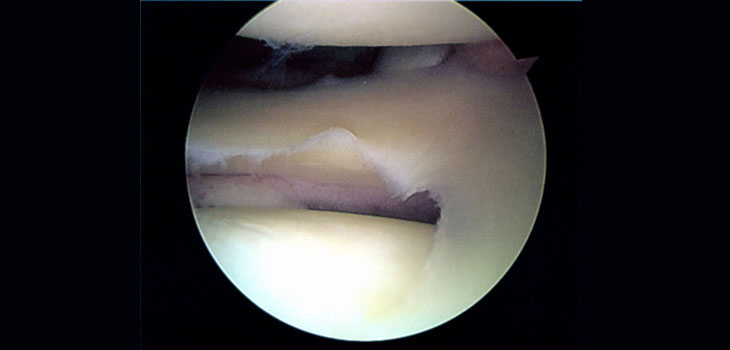

In the typical procedure the surgeon inserts a scope through a small incision to examine the joint and, if required, also partially removes the damaged cartilage through another incision. The Finnish study found that this procedure conferred no more benefits to the patient than did a sham operation.

Both groups then underwent arthroscopy. Surgeons inserted a scope into the keyhole so they could look at the torn cartilage, but only one group actually had part of the cartilage removed. Neither the patients nor the people caring for them knew which patients had undergone the real procedure and which had just had the sham operation.